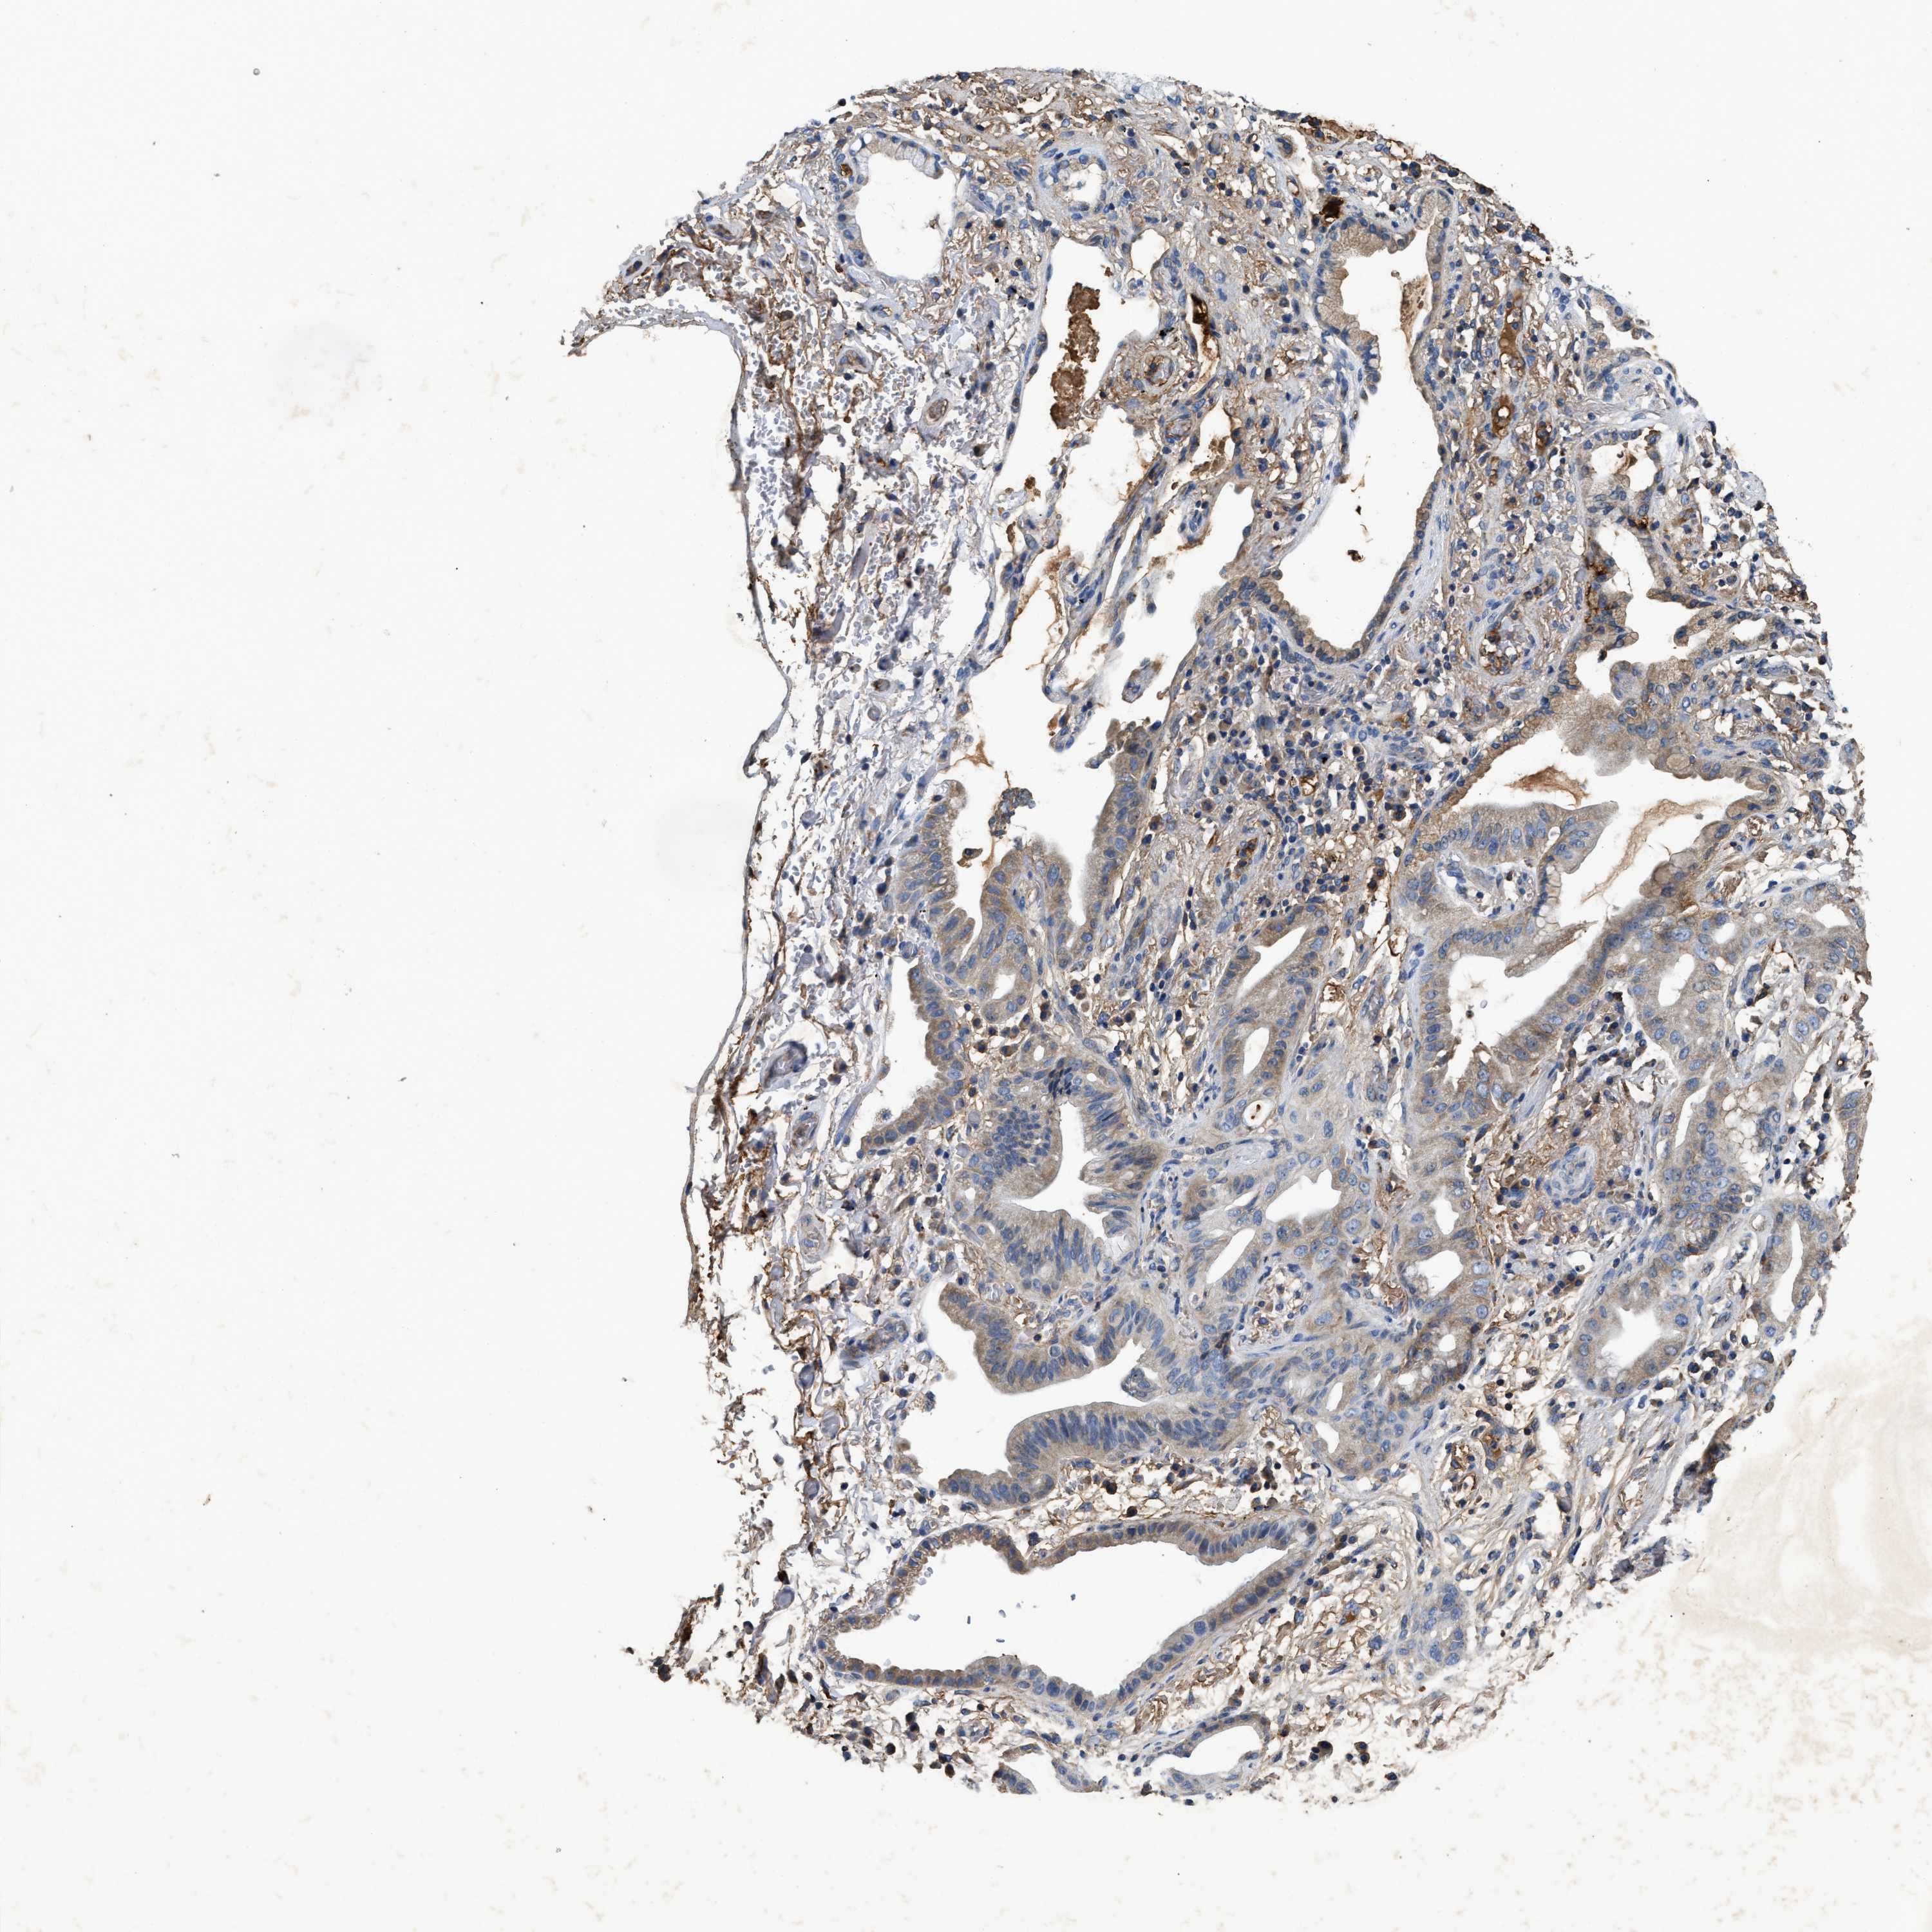

CANCER LUNG CANCER Show tissue menu

Lung cancer

Human cancer